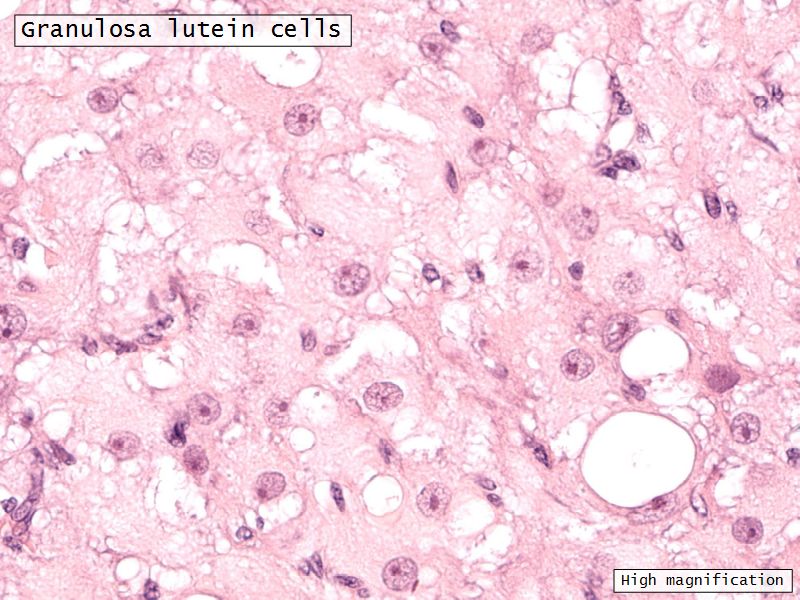

Granulosa lutein cells

- Modified granulosa cells

- Large - 30µm

- Pale cells